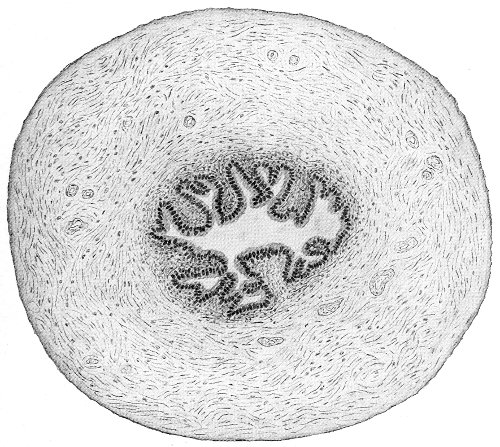

The vagina extends, as a transverse slit in the pelvic floor, upward and backward, approximately in the direction 60 of a line drawn from the ostium vaginæ to the fifth sacral vertebra. It is approximately parallel with the conjugate of the brim, so that when the woman is erect the long axis of the vagina is inclined at an angle of 60° to the horizon. The vagina is not a vertical open tube: it is a slit in the pelvic floor, in health always closed by the accurate apposition of the anterior and posterior walls (Fig. 21). The anterior vaginal wall is about 2½ inches long in a vertical mesial line. The posterior vaginal wall is about 3½ inches long. The vaginal walls are triangular in shape, being broader above than below. The shape of the normal vagina at the pelvic outlet is shown by Fig. 23. The section here shows the vaginal 61 slit of the shape of the letter H. The portions of the slit extending backward and somewhat outward are called the vaginal sulci or furrows. They are directions of diminished resistance in which tears are liable to occur.

Fig. 23.—Section illustrating the characteristic form of the vaginal cleft (Henle): Ua, urethra; Va, vagina; L, levator ani; R, rectum.] 62